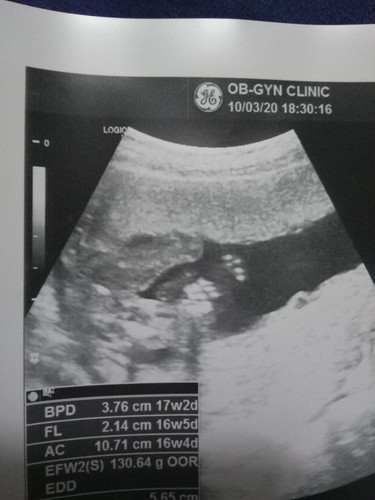

เพศลูก

ผู้หญิงหรือผู้ชายคะ ช่วยดูหน่อยค่ะ

น่าจะผู้หญิงนะค่ะแม่

น่าจะหญิงค่ะ

ผู้หญิงจ้า